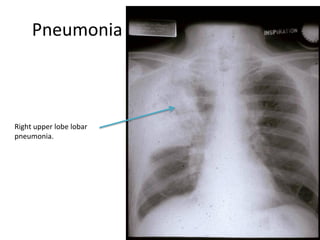

Pneumonia

Right upper lobe lobar

pneumonia.

PA and Lateral films of RUL pneumonia